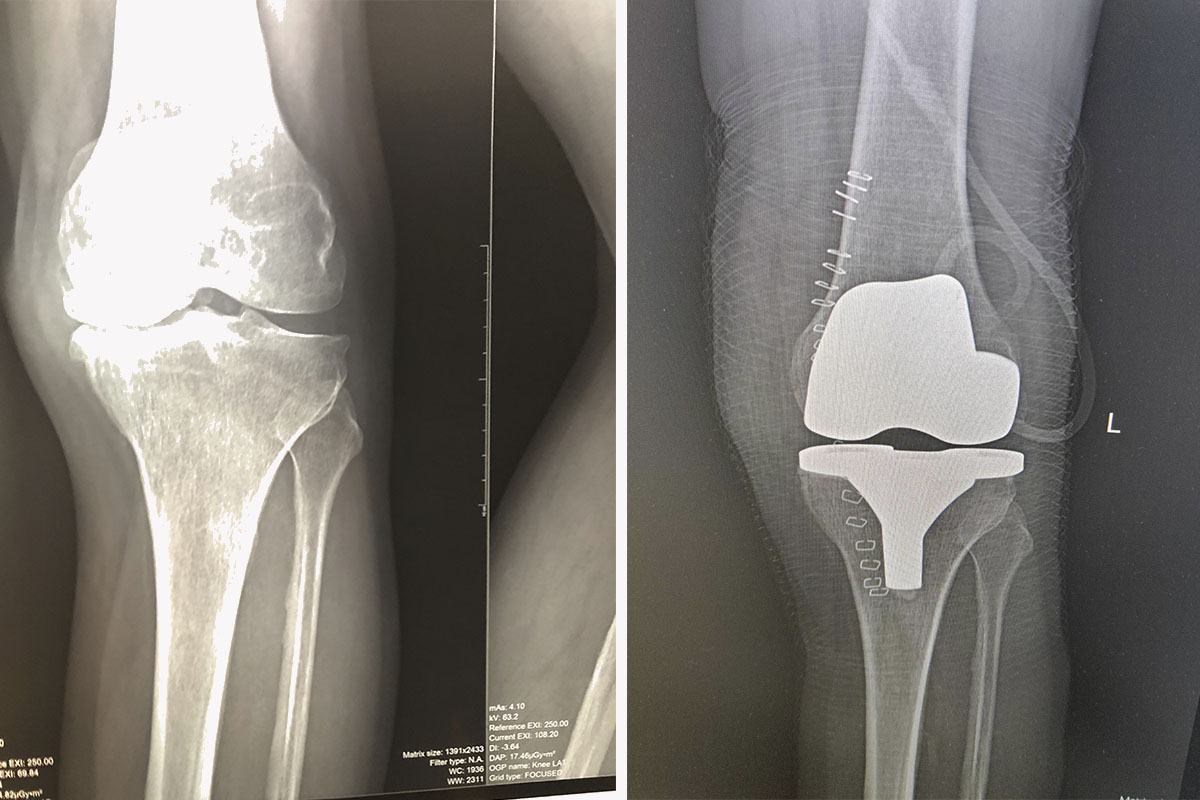

Конструкция эндопротеза коленного сустава состоит из четырех частей:

- Бедренная часть протеза. Представляет собой полусферическое металлическое изделие, повторяющее форму головки бедренной кости.

- Большеберцовая часть эндопротеза – металлическая «платформа», которая крепится на верхнюю часть большеберцовой кости. Для надежной фиксации «платформы» используется «шип», который крепится внутрь большеберцовой кости.

- Накладка на металлическую «платформу», которая выполняет функцию мениска. Чаще всего накладка изготовляется из качественного полиэтилена, который не вступает в реакцию с химическими соединениями, солями и кислотами.

- Искусственные коленные чашечки. Второстепенная часть протеза, которая помогает фиксировать и регулировать движение бедренной и большеберцовой головок.

Искусственный эндопротез представляет собой достаточно точную механическую копию естественного сустава. Протезы производятся из высококачественных материалов, что помогает снизить возможные осложнения в послеоперационный период (отторжение, воспалительные процессы, быстрый износ полиэтиленовой вкладки и т.д.)

Тотальное эндопротезирование – полноценная замена износившихся или деформированных элементов на современные протезы. Также важно уточнить, что при тотальном эндопротезировании используются два вида протезов: